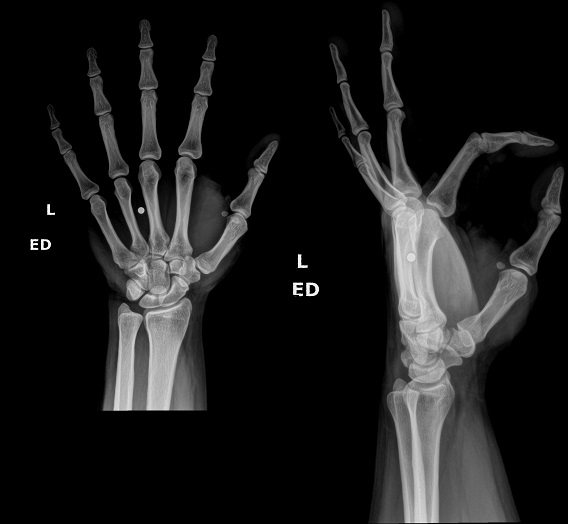

An 80 year old female presents to your office with a left ring finger deformity after a fall one week ago. She initially went to urgent care and xrays were unremarkable for a fracture (Figures 1 and 2). A photo of her left ring finger is shown in figure 3. On physical exam the left ring finger is in hyperextension at the PIP joint and flexion at the DIP joint. She able to flex her PIP joint with full motion. What is the best treatment option?